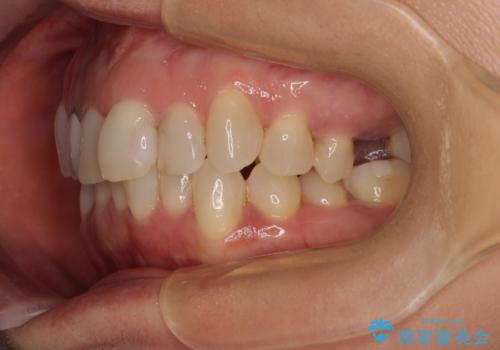

前歯のデコボコとむし歯治療の跡 インビザライン矯正とオールセラミッククラウン治療

- 前歯のセラミッククラウンの縁が見えることが気になってから、デコボコも気になるようになってきたとのことで来院された患者様です。

デコボコの程度は中等度であったため、インビザライン・モデレートパッケージにて歯列を整えることとしました。

セラミッククラウンの装着されていた前歯と、大きな修復治療の跡がある反対側の歯は、矯正治療後に補綴治療を行うこととしました。

奥歯の欠損はインプラント、ブリッジ、入れ歯のどれにすれば良いかを決められず、仕事が非常にお忙しいこともあり、保留としたまま治療を終えることとなりました。

後戻りのリスクがあるため、なるべく早めに欠損補綴治療を開始する予定です。